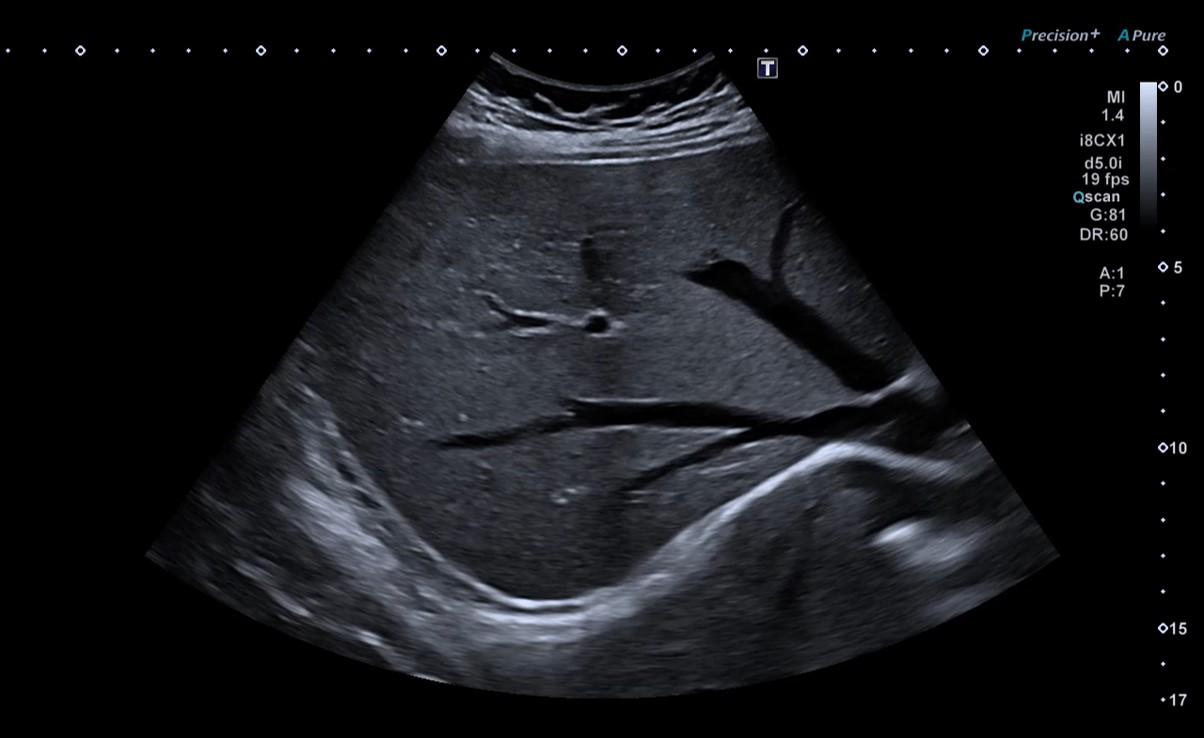

Bladder ultrasound uses high-frequency sound waves emitted by a probe. These waves travel through the tissues and are reflected back, producing real-time images of the bladder.

Bladder ultrasound is always performed via the suprapubic approach. The patient lies on an examination table in a dimly lit room to facilitate image interpretation.

The doctor applies a transparent gel to the lower abdominal skin, allowing proper transmission of the ultrasound waves and easier probe movement. The moving images are viewed in real time on a screen and interpreted by the specialist.